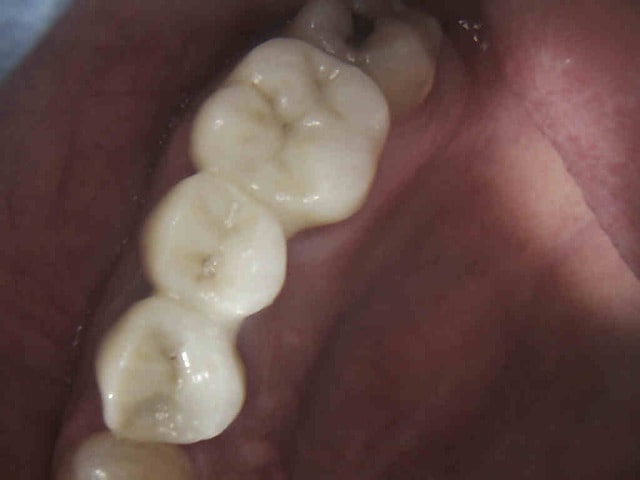

.........Et revenue aujourd'hui en urgence avec un magnifique bridge CCAM-CMU + pulpite sur 26 en option. (bridge 1 mois). Option pèche sur 14 à venir sous l'ic également.

J'y ai collé un amalgame au pouce histoire de faire plus vrai.-)))))

Costaud le full zircone

Tu vois casa je sais faire des cavités d'accès discrètes quand je veux.-))))